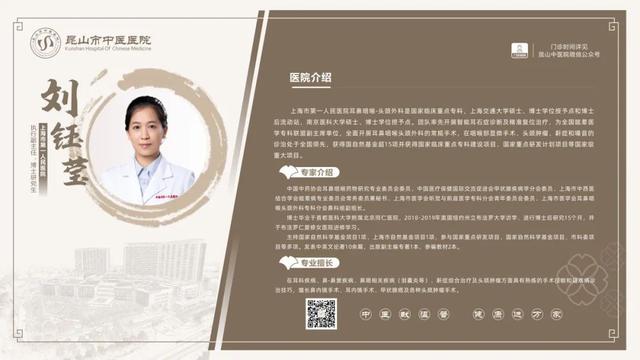

6��23��-6��29��������ר�ҳ���һ����

6��23��-6��29�������dz���ר�ҽ���